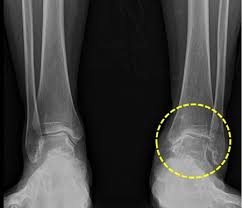

진단

의사는 발목통증의 원인을 찾기위해 다양한 검사를 할것입니다

- x레이나 ct, mri등 스캔 촬영